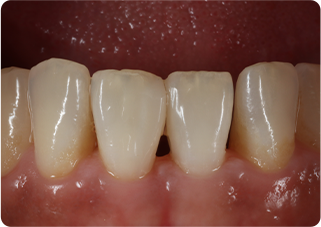

セラミッククラウン症例②

術前

仮歯

術後

| 主訴 | 前歯を綺麗にしたい、隙間が気になる |

|---|---|

| 治療期間/回数 | 4ヵ月、6回 |

| 価格(税込) | 792,000円(税込) |

| リスク・副作用 | セラミック破損の可能性 |

| ポイント | 仮歯で歯ぐきの状態を整え、自然な色、形となるようにオーダーメイドでセラミックを盛り、クラウンを作製した。 |